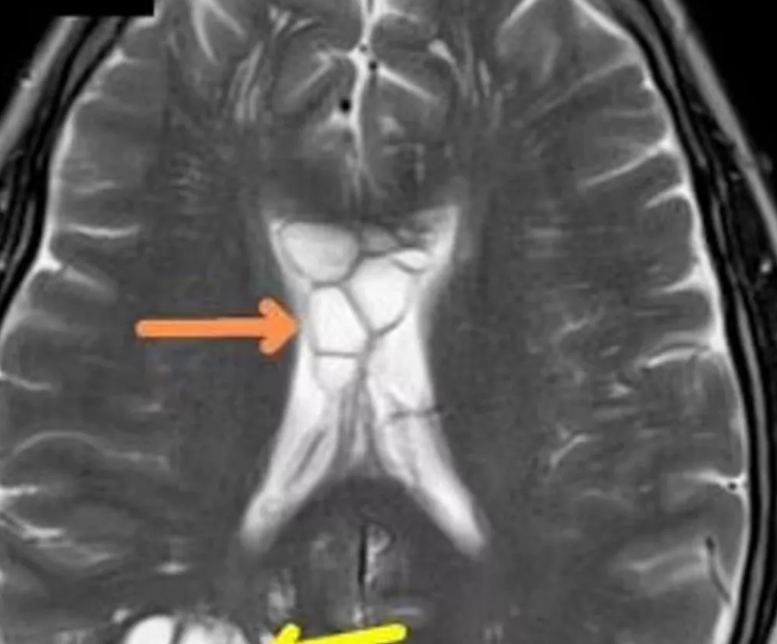

وقالت صحيفة "ديلي ستار" أن المريض البالغ من العمر 52 عامًا، والذي لم يذكر اسمه، من ولاية فلوريدا بالولايات المتحدة، بدأ ينتابه القلق الشديد بعد أن توقف الدواء الذي يتناوله لعلاج الصداع المزمن عن العمل، ولا سيما أن الصداع صار يحدث بشكل متكرر وحاد خلال أربعة أشهر متتالية. وتبين بعد الفحص وجود كيسات متعددة في دماغ الرجل بالإضافة إلى تورم، أكد الخبراء أن سببه وجود دودة شريطية وضعت بيضها في دماغه، وأن البيض كان يتسبب في تهيج الأنسجة الموجودة أسفل جمجمته مما يسبب له نوبات الصداع تلك.

وتحدث هذه الحالة، المعروفة باسم "عدوى الكيسات العصبية الطفيلية"، عندما تلتهب أجزاء من الجسم نتيجة لإصابة الدودة الشريطية. ويعتقد الأطباء أن الطفيل دخل جسد المريض بعد أن تناول طعاما غير مطبوخ جيدا ثم انتقل من الأمعاء إلى الدماغ عبر مجرى الدم.

تم نقل الرجل الذي لم يذكر اسمه في دراسة الحالة إلى وحدة العناية المركزة وتم إعطاؤه دواءً لتقليل التورم في دماغه ومنذ ذلك الحين، اختفت خراجاته ولم يعد الصداع النصفي لديه بنفس الشدة.